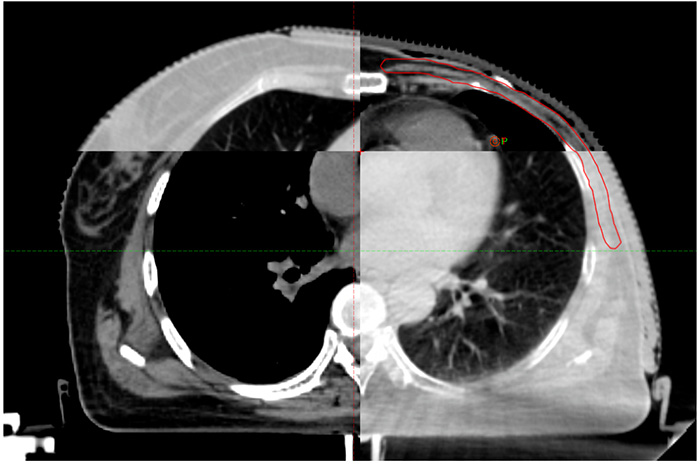

Figure 3 shows the comparison of CT images between Free Breathing (FB) and DIBH scans of the same patient, where image a is an FB scan with a distance of 1.36cm between the heart and chest wall, and image b is a DIBH scan with a distance of 2.57cm between the heart and chest wall. It can be seen that DIBH scanning increases the distance between the chest wall target area and the heart compared to FB scanning.

Figure 3: DIBH CT and FB CT images